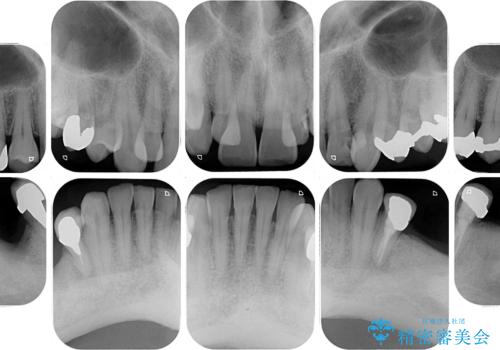

奥歯の欠損と前歯のデコボコを治したい インプラントと矯正治療の総合歯科治療

- 下顎両側の欠損と上顎前歯のデコボコを気にして来院された患者様です。

デコボコは今まで気にせずにいたそうですが、奥歯の欠損改善を機に、矯正治療に興味があるので、相談したいとのことでした。

奥歯に欠損が多く、矯正治療はやや難航することが予想されますが、患者様の希望もあり、上顎左右小臼歯を1本ずつ抜歯し、ワイヤー装置にて矯正治療を行うこととしました。

矯正歯科治療を行うに当たり、痛みや違和感を感じている歯の根管治療を行い、矯正治療中にインプラント埋入し、補綴治療と矯正治療を同時に終了できるように進めて行くこととしました。